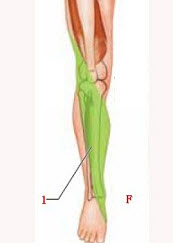

如图中箭头所示范围感觉区的脊髓中枢为( )

A:L

1

B:L

2

C:L

3

D:L

4

E:L

5